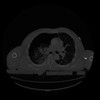

28 CUERPO,CE,Vol,2.0,CUERPO,,